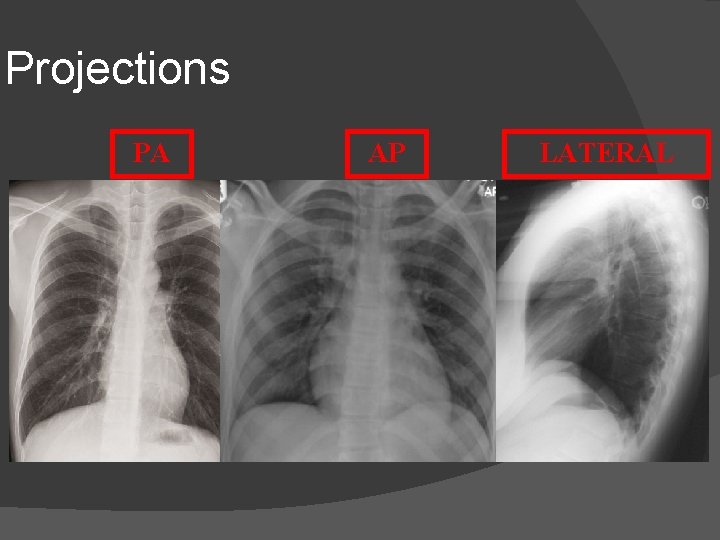

Projections PA AP LATERAL